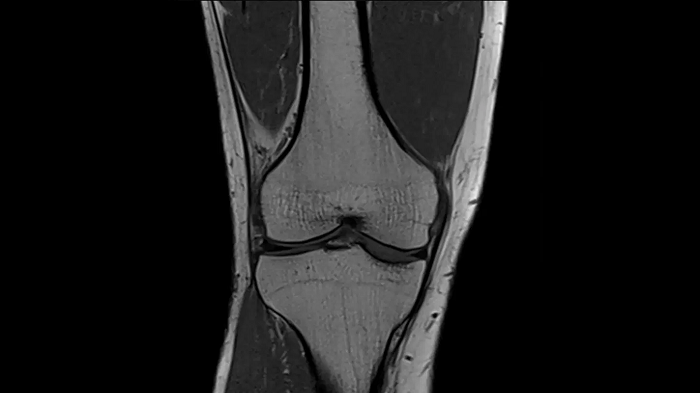

PD TSE Fat Sat with Deep Resolve and Simultaneous Multi-Slice

For clear imaging of the knee, outstanding fat suppression and performance are possible. Integrating the influence of Deep Resolve with the established Simultaneous Multi-Slice technique.

SMS 2 | Deep Resolve Gain & Sharp

0.4 x 0.4 x 3.0 mm2

TA 2:56 minutes

MAC-ID: 7aaaa0198.